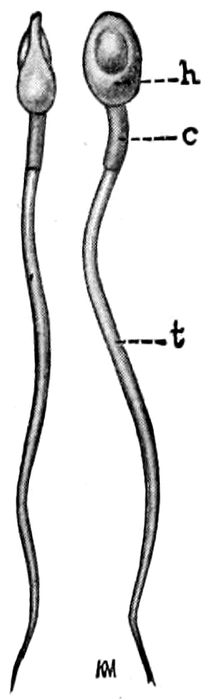

The Mammary Glands.—The mammary glands are

secondary but highly important parts of the genital system.

They are formed by a dipping down of skin glands

and they perform the special function of secreting milk.

The breast is made up of fifteen or twenty lobes, each

of which, like a bunch of grapes, clusters about and

discharges into a single tube which, in turn, leads to

the nipple. The area between the lobes is filled with

fat and connective tissue.

Fig. 8 A.—The excreting ducts of the mammary gland. (Lenoir and Tarnier.)

Fig. 8 B.—Lobules and duct of the mammary gland. (Lenoir and Tarnier.)

Fig. 9.—Nipple, areola, and the glands of Montgomery. (Eden.)

The nipple is pink or darkly pigmented. It is composed

of erectile tissue and under stimulation, it rises

from the surface of the gland so that it is easily taken

into the mouth.

Fig. 10.—Supernumerary milk glands in the axillæ. They may be found also below the breasts. (Witkowski.)

Fig. 11.—The three ages of the breast—virginity, maturity, and senescence. (Witkowski.)

Surrounding the nipple is a darkly pigmented area

from one inch to four inches in diameter that is called

the areola. It contains hard, shot-like nodules, the

glands, or tubercles, of Montgomery. These often secrete

milk and sometimes become infected. It occasionally happens

that more than two breasts may be found on the

human female, and not infrequently pieces of mammary

32tissue may be discovered in the axilla or on the chest or

back.

The mammary gland is undeveloped at birth, but, nevertheless

it may fill with milk (witches’ milk). At puberty,

after marriage, and during pregnancy, the gland

reaches maturity. It is only after delivery, however,

that the functional climax is attained.